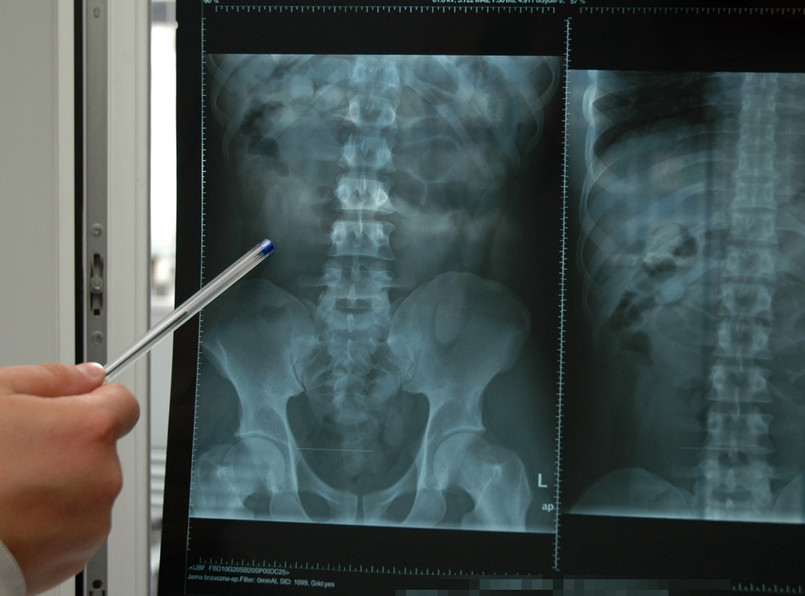

Zdjęcie RTG żołądka jednego z przemytników

To był strzał w dziesiątkę. Na zdjęciu RTG żołądków obu mężczyzn zobaczyli bowiem kapsułki wypełnione kokainą. Gwinejczyk połknął 140 sztuk, Polak - 83.

Każdy pakunek ważył około 10 gramów. W sumie w żołądkach przemytników tkwiły ponad dwa kilogramy kokainy. Całość warta jest około 500 tysięcy złotych.